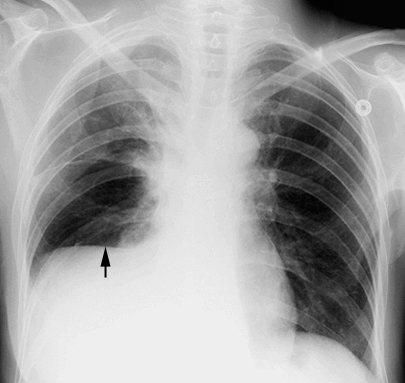

Example 4

Diagnosis

Right Sided pleural Effusion